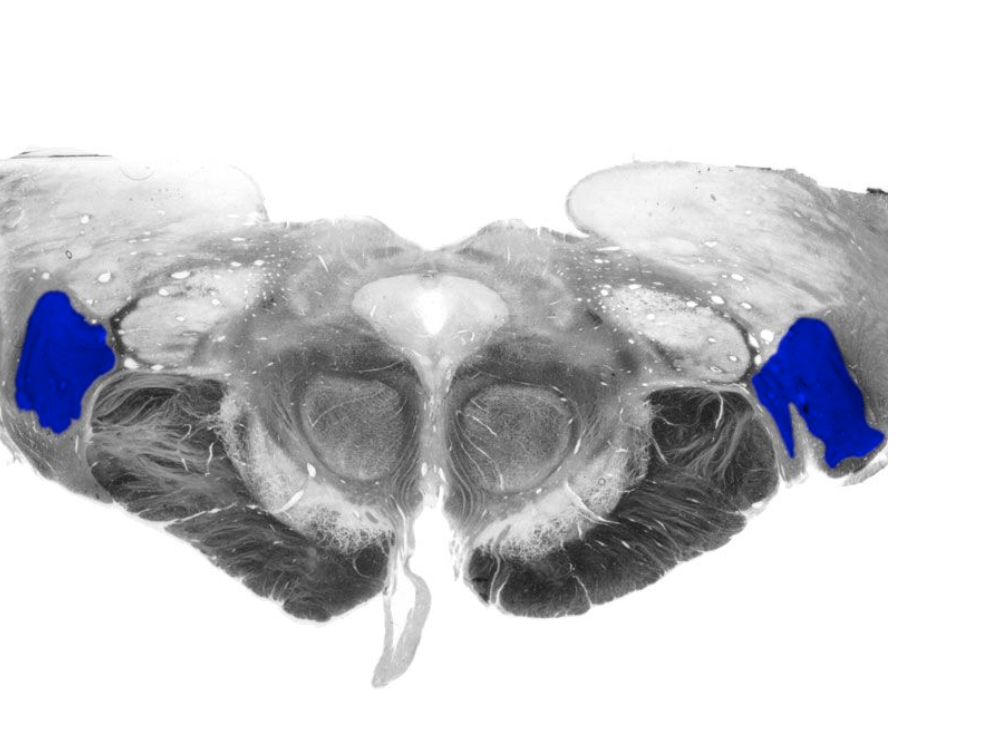

Dorsal column nuclei

Gracile nucleus and cuneate nucleus; contain the second-order sensory neurons that relay mechanosensory information from peripheral receptors in the body (excluding the face) to the thalamus via the medial lemniscus. The dorsal column nuclei are located in the lower medulla.

Nucleus cuneatus

Dorsal column nucleus in the lower medulla; contains second-order sensory neurons that relay mechanosensory information from peripheral receptors in the upper extremities to the thalamus via the medial lemniscus.

Nucleus gracilis

Nucleus containing the second-order sensory neurons that relay mechanosensory information from peripheral receptors in the lower body to the thalamus via the medial lemniscus, located in the lower medulla (also called the "gracile nucleus"). The nucleus gracilis also relays visceral pain information from second-order neurons in the central spinal cord to the thalamus.